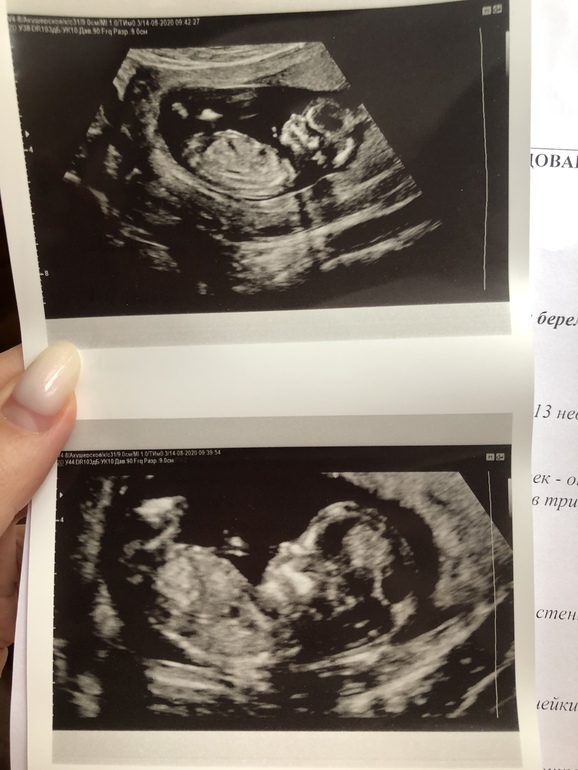

Девочки, кто-то видит пол? На узи говорят, что девочка, у кого ошибались на первом скрининге? Срок 13 недель и 1 день

Если предположить что эта точечка бугорок, то девочка

Ну и по форме головы на девочку похоже

Мне в 13 недель сказали с 90% вероятностью, что девочка - не ошиблись)

У Вас на фото не видно пол.. Но почему то мне кажется, что на девочку похоже)

Мне в 12+2 точно сказали, что девочка будет. Здесь, на втором снимке, я бы тоже на девочку поставила)

На этих фото не видно пол

Я просто и на узи и тут пыталась что-то рассмотреть, но мне кажется он в таком положении лежал что ничего не видно было)